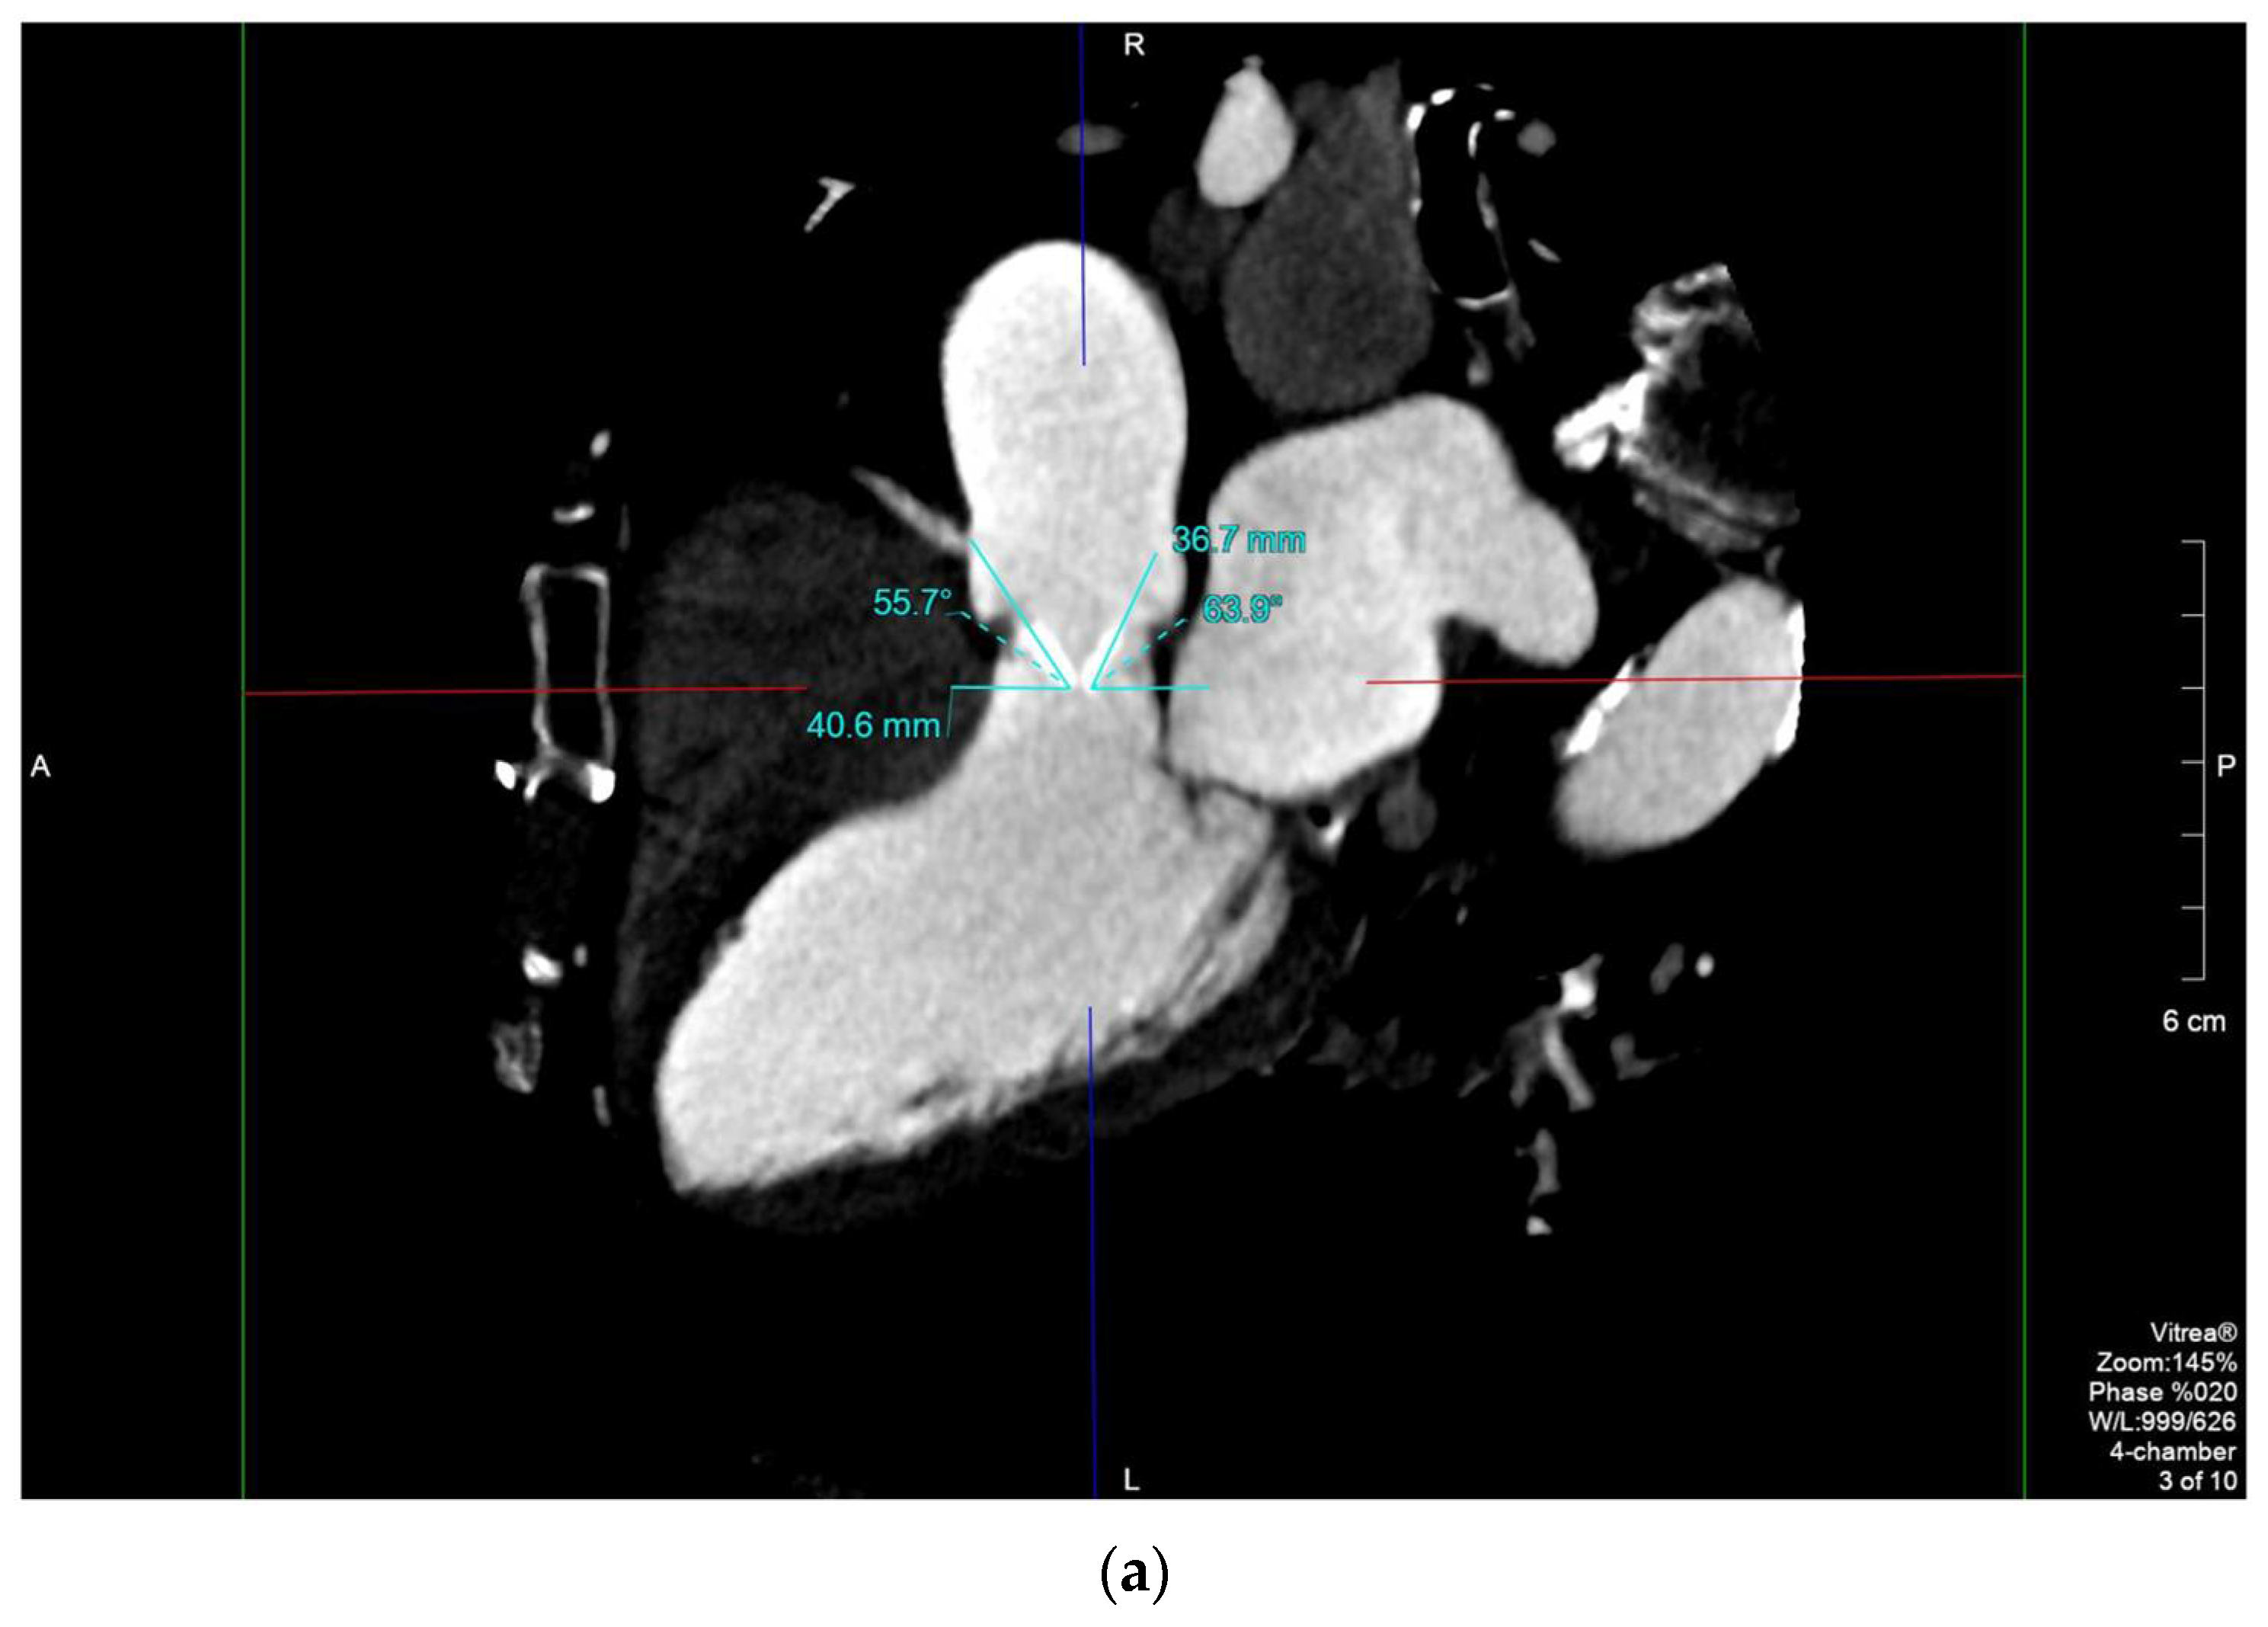

2.1. Case 1